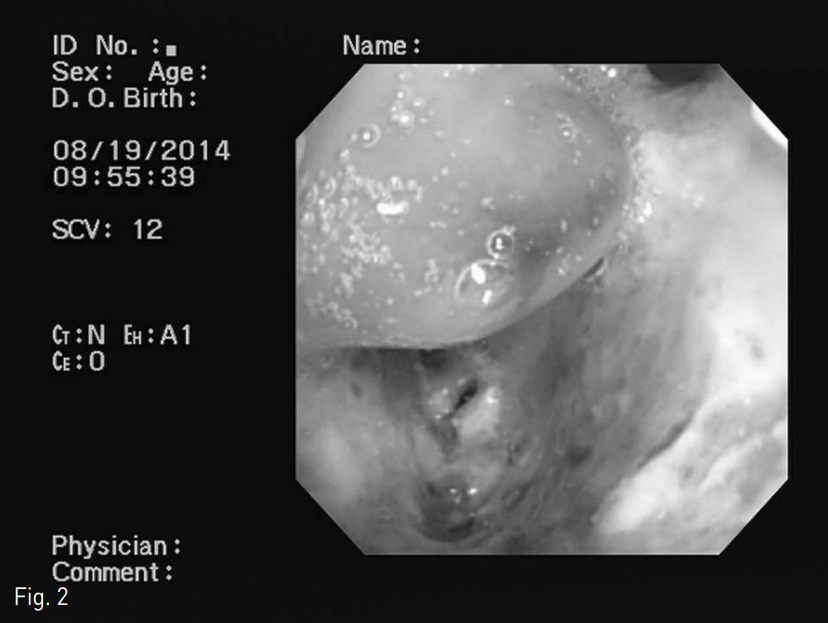

Fig. 2

Bronchoscopy shows mucosal destruction with yellowish exudate in right lower bronchus.